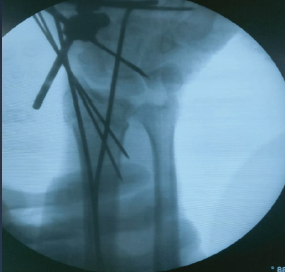

A Case Series of Functional and Radiological Outcome of Comminuted Distal Radius Fractures Treated with Bridging External Fixator with Optional Percutaneous K-wires

Subramanya Gandhi , Mohamed Safiullah , Vijay Narasimman Reddy , Ashin khan , Mervin Rosario P M